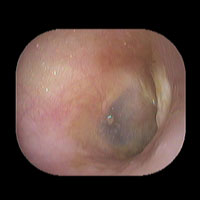

右急性中耳炎(中等症)

鼓膜がやや赤くなっています。鼓膜の奥に膿が透けて見えています。鼓膜の腫れはありません。抗生剤の内服で鼓膜切開を行わずに16日目で治りました。

初診日